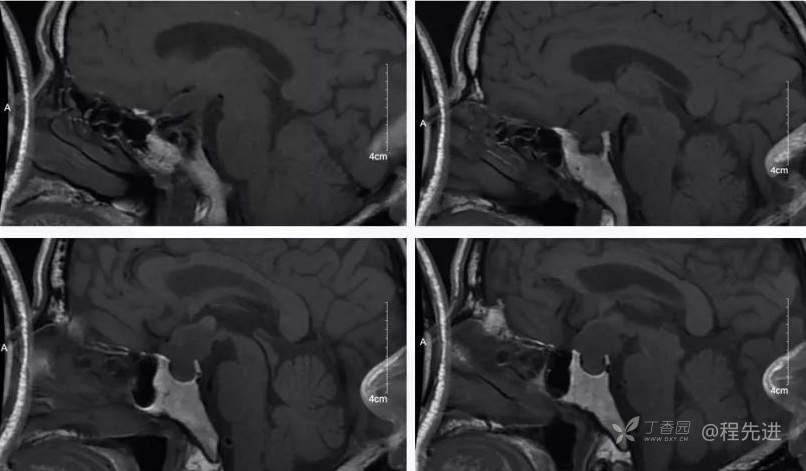

MR

T1冠状位